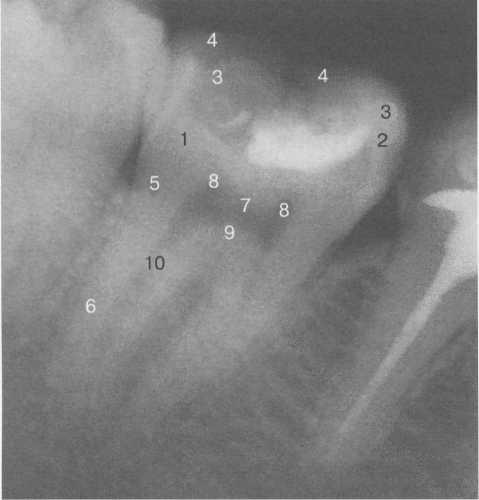

Рис. 20.11. Рентгенограмма второго моляра нижней челюсти.

1 — коронка зуба; 2 — эмаль коронки зуба; 3 — язычные бугры; 4 — небные бугры; 5 — шейка зуба; 6 — корень зуба; 7 — пульпарная камера; 8 — рога пуль-парной камеры (медиальные и дистальные); 9 — дно пульпарной камеры; 10 — корневой канал.